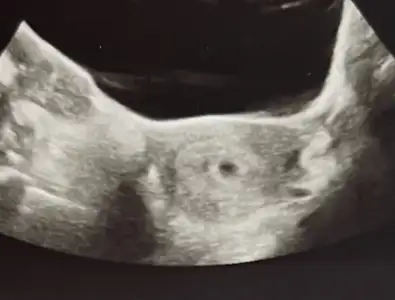

Ben doktordan çıktımm kese göründü 💃🏻 sağlıklı dedi 3-4 gün büyük gibi düşün erken döllenme dedi betadan. Tekrar kan vermene gerek yok 14 gün sonra gel dedi. Kan testi yaptıracağımm bir de d vitamini verdi

kalbi duymadık onun için 4-5 gün sonra gelmen lazım ama sen yine de 14 gün sonra gel dedi. Benim döngüm 25-26 gün olduğu için sat günü aynı olan insanlardan 3-4 gün önde olacaksın erken yumurtladığın için dedi çünkü programlar genelde 28-30 güne göre. 6 ağustos doğum tarihi olabilir dedi❤️ beslenme konusunda öneriler verdi kesenin yeri şekli güzel dedi karından görebildi. Çok teşekkür ederimmmm❤️❤️